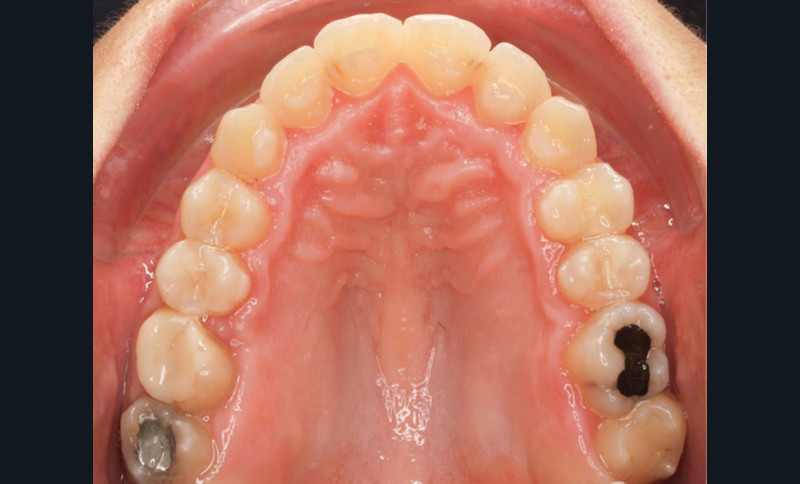

Diagnostic (fig. 1a-g)

La patiente présente une classe III squelettique dans un contexte hyperdivergent associée à une endoalvéolie maxillaire, un articulé inversé antérieur, une rétroversion incisive maxillaire, des rapports de classe I canine bilatérale, une absence de 16 et 36.

Le sourire est étroit, dégradé par les malpositions dentaires.